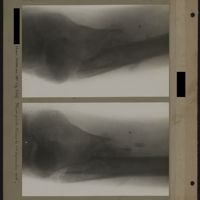

0033 - Page 29 - [Radiographies de la cheville, du tibia et de la fibula]0033 - Page 29 - [Radiographies de la cheville, du tibia et de la fibula]